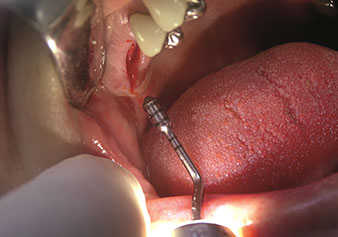

One application, which is often underestimated is the atraumatic extraction of tooth roots or root fragments in the scope of alveolar management. The fine periotomes, which are currently available in two versions (EX1 and EX2 from W&H), can also be used to remove teeth which have previously undergone special endodontic treatment or ankylosed roots with ease. This results in extraction alveoli where both the hard and soft tissue are fully intact as it is generally possible to avoid reflection.

This establishes the optimal basis for subsequent or immediate implant treatment (Figures 1 and 2 included with the kind permission of Dr Torsten Conrad, Bingen a. Rhein).